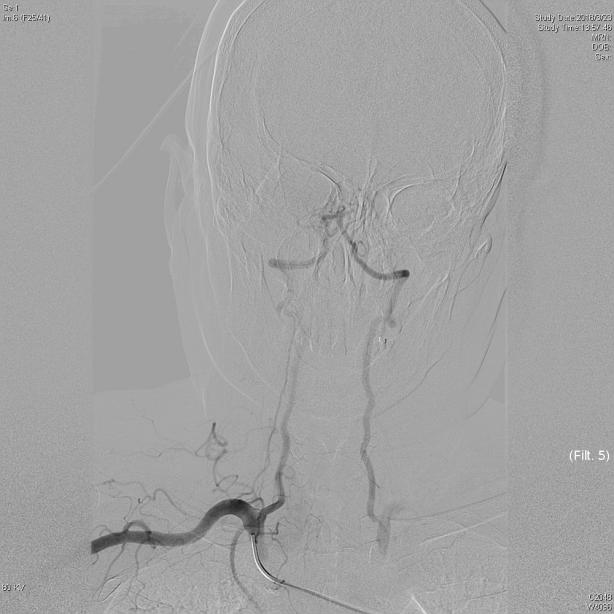

图1左侧锁骨下动脉闭塞,箭头所指               图2 经右侧椎动脉造影:可见血流自左侧椎动脉向远

端逆向供应左侧锁骨下动脉,颅内大脑后动脉显影不佳